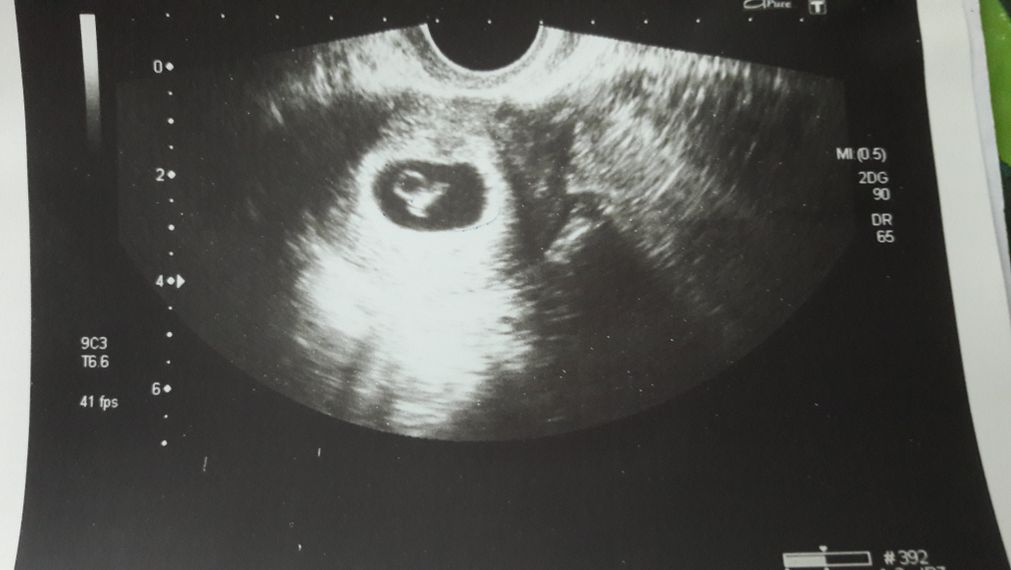

Фотографии на ранних этапах беременности